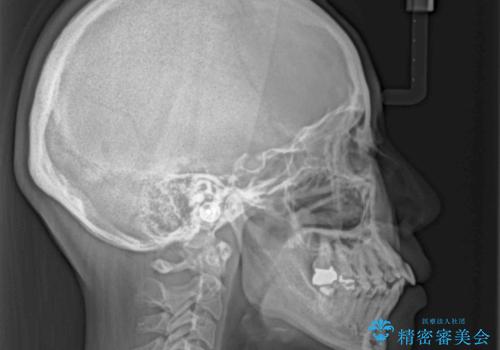

通常であれば上下左右の第一小臼歯4本を抜歯して口元の突出感を改善しますが、下顎前歯が1本欠損しており、上下の歯の数がアンバランスであるため、4本抜歯するかどうか悩むところでした。

上顎前歯はやや小さめで、下顎前歯はやや大きめであったため、上下左右4本を抜歯しても左右奥歯の咬み合わせは理想に近い状態を達成できると判断し、上下左右の第一小臼歯4本を抜歯し、ワイヤー装置にて矯正治療を行うこととしました。